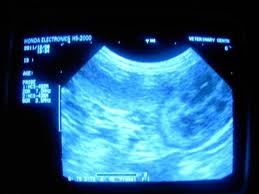

Киста простаты на УЗИ

Киста простаты - это небольшие водяные пузырьки. Выявляются у 7,9% до 20% мужчин. Мелкие кисты (2-5 мм) могут встречаться у практически здоровых мужчин.

Часто кисты располагаются в области основания предстательной железы, в области внутреннего отверстия уретры. Для врожденных характерно срединное расположение в основании предстательной железы, каплевидная или веретенообразная форма с тонкой ножкой из паренхимы. Содержимое таких кист анэхогенное однородное, стенка тонкая, размеры от 0,3 до 4 Могут быть многокамерными.